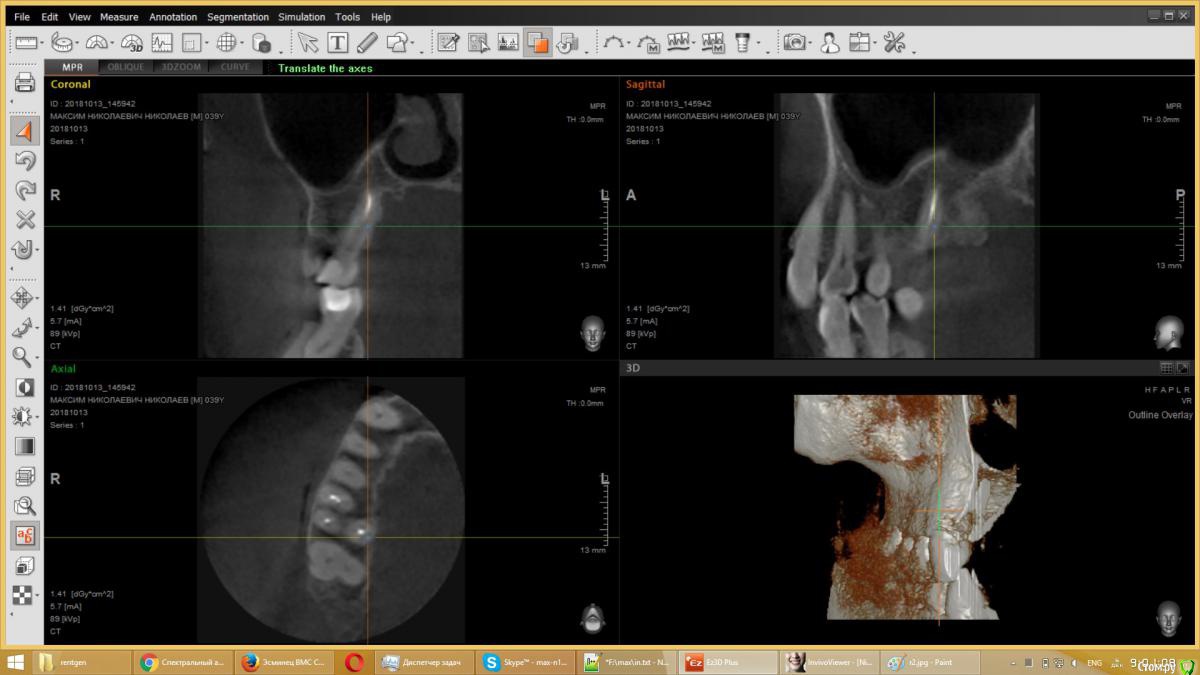

usilitel Опубликовано 4 декабря, 2018 Поделиться Опубликовано 4 декабря, 2018 (изменено) 10 месяцев назад депульпировали верхнюю 6-ку, с тех пор мучаюсь неврологическими симптомами (онемение, давление, зуд). На снимке с зубом всё нормально. Возможная причина - небольшое количество материала вышло в гайморову пазуху (но осталось под слизистой). Я думаю что этот материал мог задеть нерв, отсюда и симптомы. Зуб вырывать врачи отказываются, т.к. показаний к удалению нет. К тому же может не помочь.Хочу вынуть материал из гайморовой пазухи, но непонятно как это сделать. Прошу совета.Возможный варианты:1) Оставить всё как есть. Меня этот вариант не устраивает, т.к.: 1) материал может быть причиной проблем с неврологией, и его удаление может решить проблему. 2) зуб все равно рано или поздно придется удалять, не хотелось бы чтобы после удаления зуба в организме осталось инородное тело.2) Вынуть эндоскопом сверху. ЛОР сказал что так сделать нельзя, т.к. поскольку материал под слизистой - сверху его не увидишь. Правда можно содрать слизистую и всё-таки достать материал, но вред от такого действия многократно превысит пользу.3) При удалении зуба вынуть материал снизу. По словам хирурга - стоматолога - это сделать нереально, т.к. для этого придется разрезать перегородку, отделяющую гайморову пазуху, и она потом сама не заживёт.4) Надеяться, что матерал сам выйдет вместе с зубом при удалении зуба. Вариант крайне маловероятный, т.к. при удалении зуба материал практически наверняка останется в пазухе.5) Распломбировать канал, протолкнуть материал дальше в гайморову (чтобы он вышел за слизистую), а потом вынимать сверху эндоскопом. Не уверен что найду терапевта который согласится это сделать.6) Сразу после удаления зуба протолкнуть материал дальше в гайморову (чтобы он вышел за слизистую), а потом вынимать сверху эндоскопом. Не уверен что найду хирурга который согласится это сделать. PSЗуб мне не жалко, всё равно рано или поздно его надо будет удалять. Изменено 4 декабря, 2018 пользователем usilitel Ссылка на комментарий

usilitel Опубликовано 6 декабря, 2018 Автор Поделиться Опубликовано 6 декабря, 2018 выкладываю снимки Ссылка на комментарий